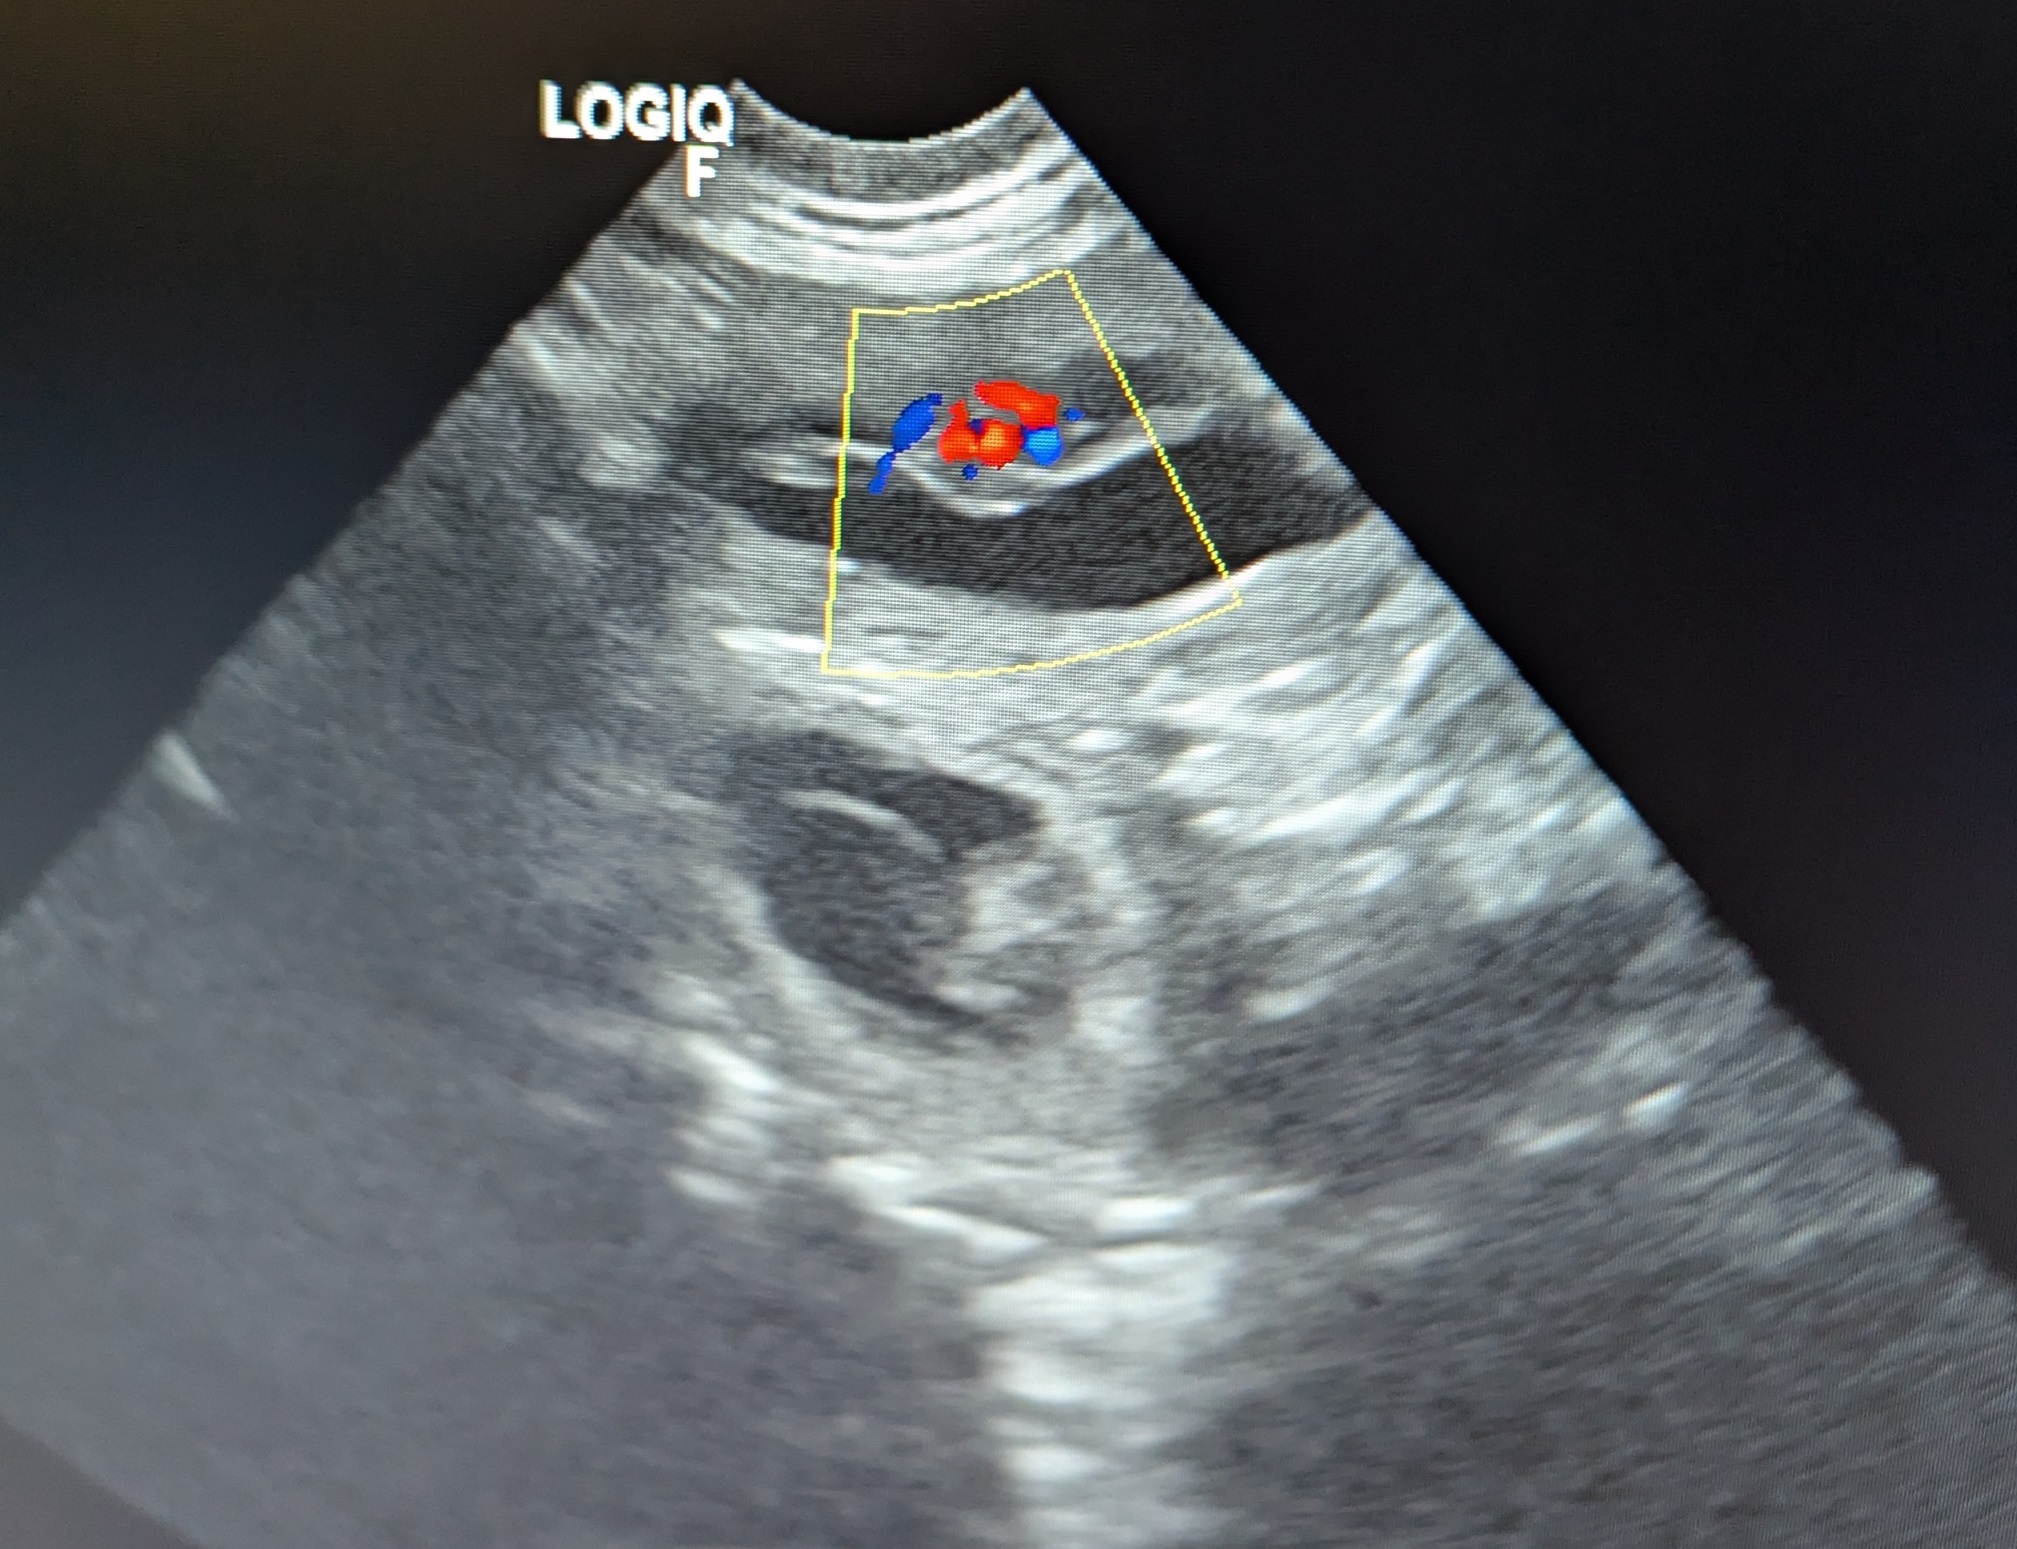

Cara bekommt Welpen ! Wir freuen uns riesig.

Cara vom Hexenwerk